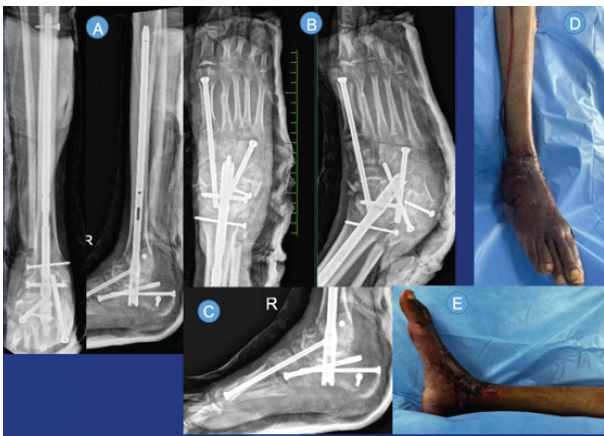

Radiographs and computed tomography (CT) were suggestive of an osteopenic bone stock, with dislocated CCJ and medially subluxed TNJ (Fig. 3). The Subtalar joint was also distracted laterally. He underwent the following procedure (Fig. 4): Tendoachilles lengthening (equinus component), Midfoot fusion (midtarsal dislocation), Ankle arthrodesis with fibula osteotomy and iliac crest bone grafting (lateral ligament complex injury and chronicity of injury).

Figure 3: (A, B) Radiographs on reception by authors. (C, D, E) Three-dimensional computed tomography scans on reception by the authors.

Figure 4: Post-operative radiographs (A, B, C) and clinical images (D, E) after ankle arthrodesis and midfoot fusion with tendoachilles lengthening and Iliac crest bone grafting.